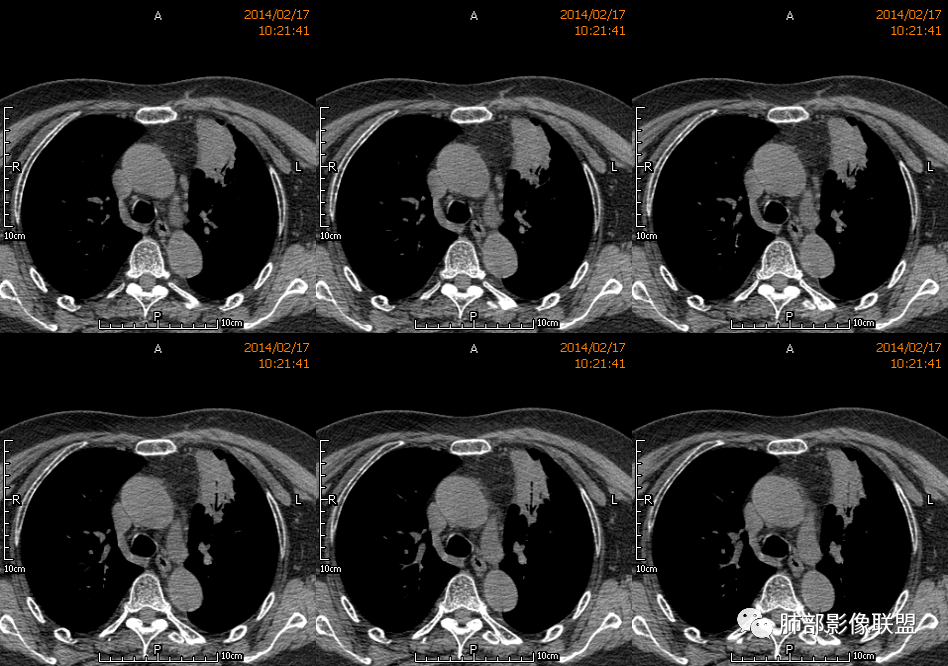

薏米: 老年女性,急性起病,咳嗽,咳痰,咯血,白细胞低,胸部CT提示左肺上叶可见一团块样密度增高影,边缘平直,部分略有膨隆,内可见支气管进入后截断,小的空洞,血管造影,坏死,明显强化,周边可见少许索条,考虑炎性病变,肺脓肿可能。鉴别结核,隐球菌。

一切∮随缘: 定位:肺内,左肺上叶肿块,呈长条状,平行血管束生长,边缘分叶,平扫密度均匀,增强后不均匀强化,可见低密度坏死,近段支气管及血管穿行病灶内,远端堵塞支气管,血管似有破坏,周围散在点状小结节,及纤维索条影,考虑恶性:腺癌,类癌,淋巴瘤。鉴别结核及隐球菌。

红星: 老年女性,咳嗽咳痰10天,痰中带血4天。左肺上叶前段胸膜下肿块影,沿支气管方向走行以膨胀生长为主,局部有收缩改变,支气管血管绝断,中间有小片状的坏死及小的空洞影,增强扫描病灶明显的强化,病灶周围网格状的小叶间隔增厚。拟左肺上叶前段浸润型腺癌并癌性淋巴管炎。鉴别诊断结核肉芽肿。

傅昌瑜: 老年女性,咳嗽咳痰10天,痰中带血4天。左肺上叶前段胸膜下肿块影,沿支气管方向走行,膨胀生长为主,局部边缘似有收缩改变,中间有小片状的坏死,支气管进入,增强扫描病灶明显的强化,血管走形较自然(血管漂浮征?),病灶周围网格状的小叶间隔增厚。考虑淋巴瘤可能性大,注意鉴别炎性肉芽肿及肺腺癌。

水晶石头: 患者老年女性,咳嗽咳痰10天,痰中带血4天余。查血常规白细胞低;肿瘤标志物、凝血功能正常;血生化:蛋白低;C反应蛋白、血沉稍升高。胸部CT:左肺上叶前段胸膜下沿气管支气管走形肿块影,长轴与胸膜平行,见分叶、毛刺、支气管截断、空泡征象。增强明显强化,且见血管造影征及病灶内小灶低密度坏死区。左肺上叶尖后段见一结节灶。综合考虑恶性病变可能大,腺癌或淋巴瘤可能。鉴别诊断肺脓肿。

尘缘: 老年女性,咳嗽咳痰10天,痰中带血4天,白细胞及中性粒明显减低,轻度贫血。影像表现:左上叶肿块,边缘膨隆,局部平直,支气管稍扩张,进入后远端堵塞,内见小空洞及不规则坏死区,增强后强化明显,坏死边界较清,并见环状强化区,内部血管走行自然,周围见小叶间隔增厚呈大网格征。初步诊断:慢性炎性伴脓肿形成及肉芽组织增生。鉴别淋巴瘤及腺癌,先抗炎治疗后复查或直接穿刺明确。

王崇军: 老年女性,咳嗽咳痰10天,痰中带血4天。左肺上叶前段胸膜下 肿块影及段形态密度增高影,沿支气管方向走行,膨胀生长为主,局部有收缩改变,支气管进入并闭塞,中间有小片状的坏死及小的空洞影,空洞漂浮在坏死边缘,增强扫描病灶明显的强化,坏死边界清楚,似乎有轻度强化环,病灶周围网格状的小叶间隔增厚及小结节影,外侧胸膜呈糊墙改变。考虑为肺脓肿,这么大的病灶,竟然没有发烧,白细胞低,CPR轻度升高,均与脓肿不符,所以恶性待排,短期抗炎治疗后复查,病灶没有变化,脓肿就可以排除,恶性基本可以确定。

2.左肺上叶前段胸膜下块状影,不规则呈“逗点样”延向肺门区,边界清楚,未见分叶、毛刺及张力,表面不规则棘突,状如“火焰”或“日冕”。相邻胸膜增厚,未见栽赃、卫星病灶。

3.病灶密度不均,中央坏死液化并见气泡影,支气管及血管贴边进入,较均匀环形强化(显示多层结构),未见明确壁结节。

4.肺门纵隔未见肿大淋巴结。

1.块影不规则,未见分叶、毛刺及张力,未见壁结节,肺门纵隔未见肿大淋巴结等,缺少肺腺癌的特征。

2.未见血管及支气管受累,用肺鳞癌不好解释,何况女性患者。

3.病灶易坏死液化,环形强化,支气管及血管贴边进入,“火焰”样边缘轮廓,更符合炎性块影的特点。